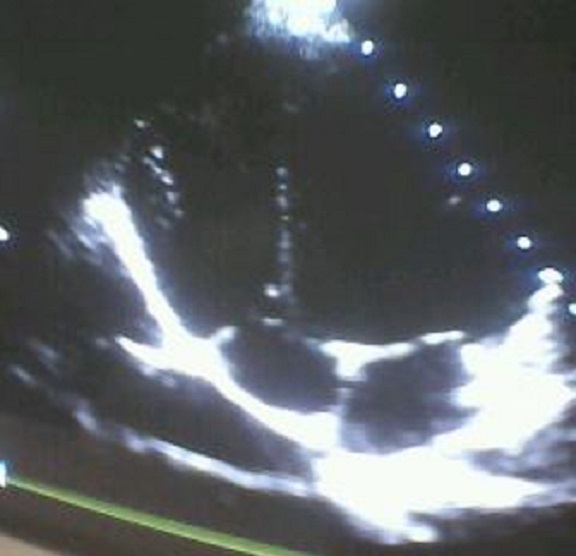

Cœur à six cavités chez un enfant de 11 ans

Nous vous présentant cet article montrant le cœur d’un enfant de 11 ans présentant une duplication totale bien segmentée du ventricule droit et de l’oreillette droite. Cette malformation a été découverte dans le cadre d’investigation des douleurs thoraciques. Ceci constitue une malformation très rare paucisymptomatique et compatible avec la vie.